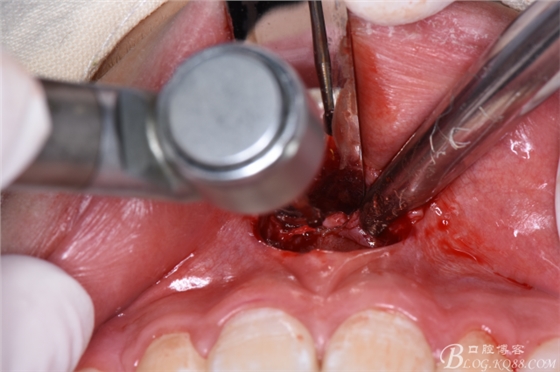

圖10.暴露出11、21之間的倒置多生牙牙冠

圖11.暴露出整個多生牙牙冠